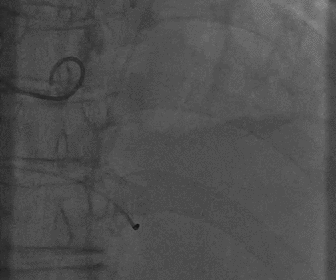

根部造影

瓣膜释放完毕